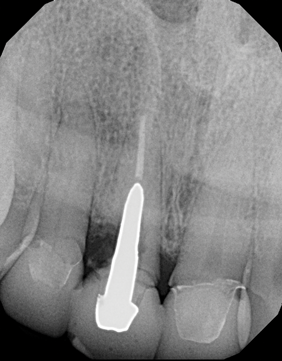

Fig 3. In a separate case, radiograph of a decayed endodontically treated tooth is shown. The decision was made to extract it before further damage to adjacent teeth and/or loss of bone could occur.

Figure 3

Fig 4. Radiograph of the implant to replace the tooth in Fig 3 (implant placed by David Levine, DDS).

Figure 4

Fig 12. In a separate case, radiograph of implant No. 8 is shown. Previous endodontically treated tooth had fractured and the decision was made within a few months to extract and replace it with an implant. Bone was preserved to optimize the implant site.

Figure 12